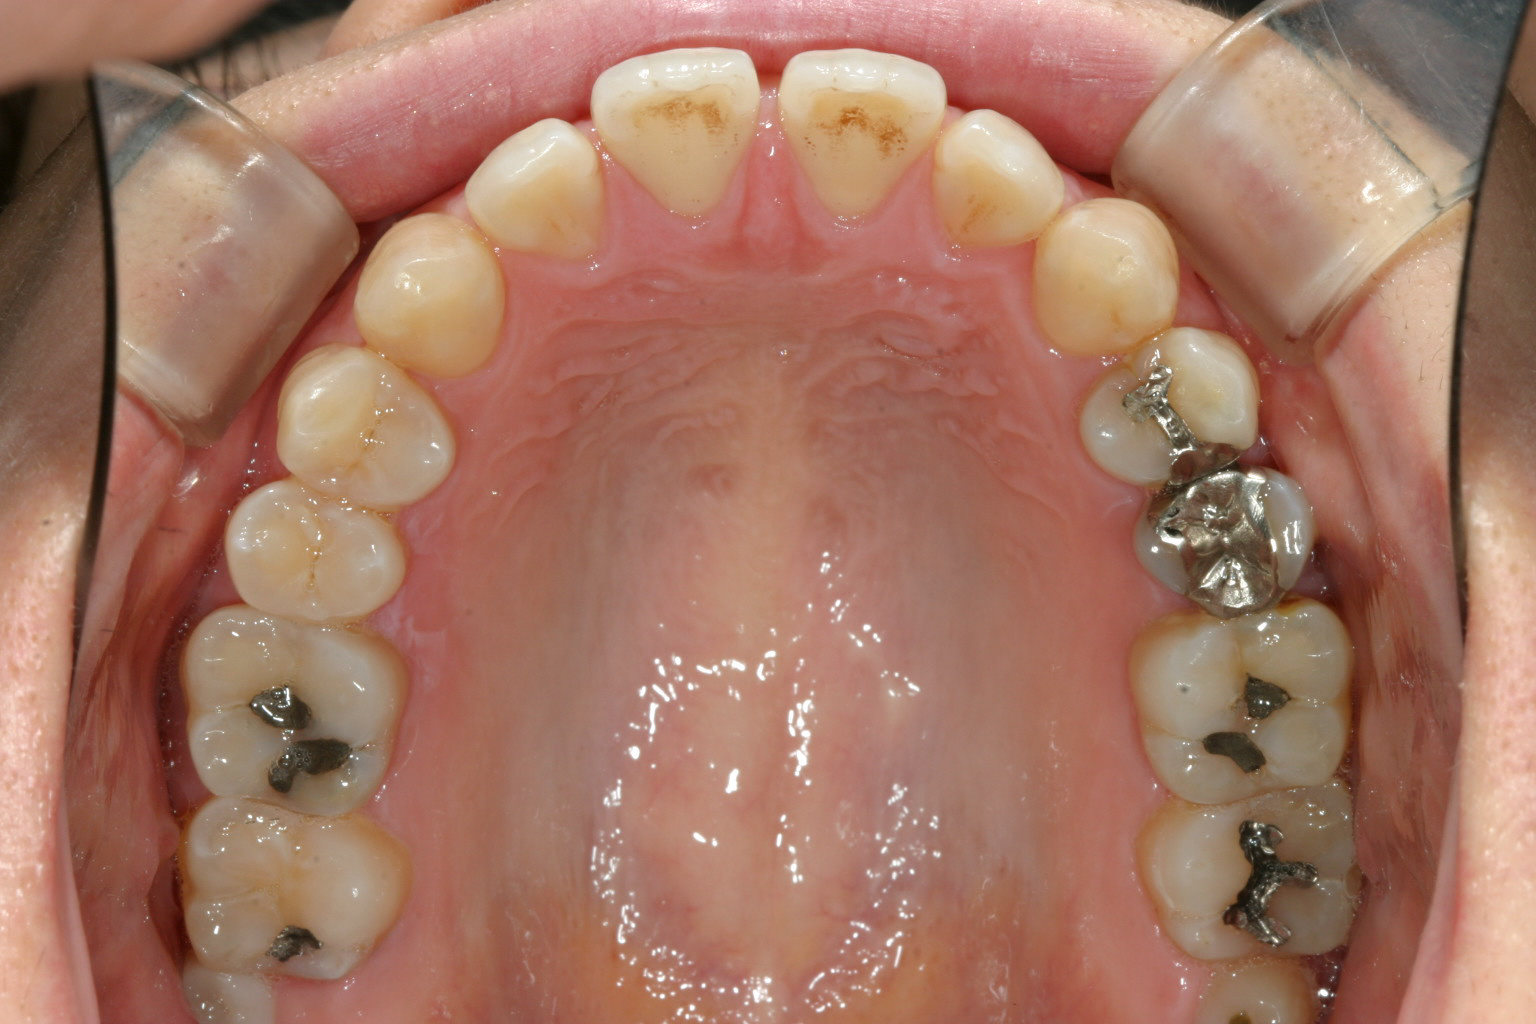

前歯部あちこちすいているのが目立ちます。

全体的に隙間を締め付けました。